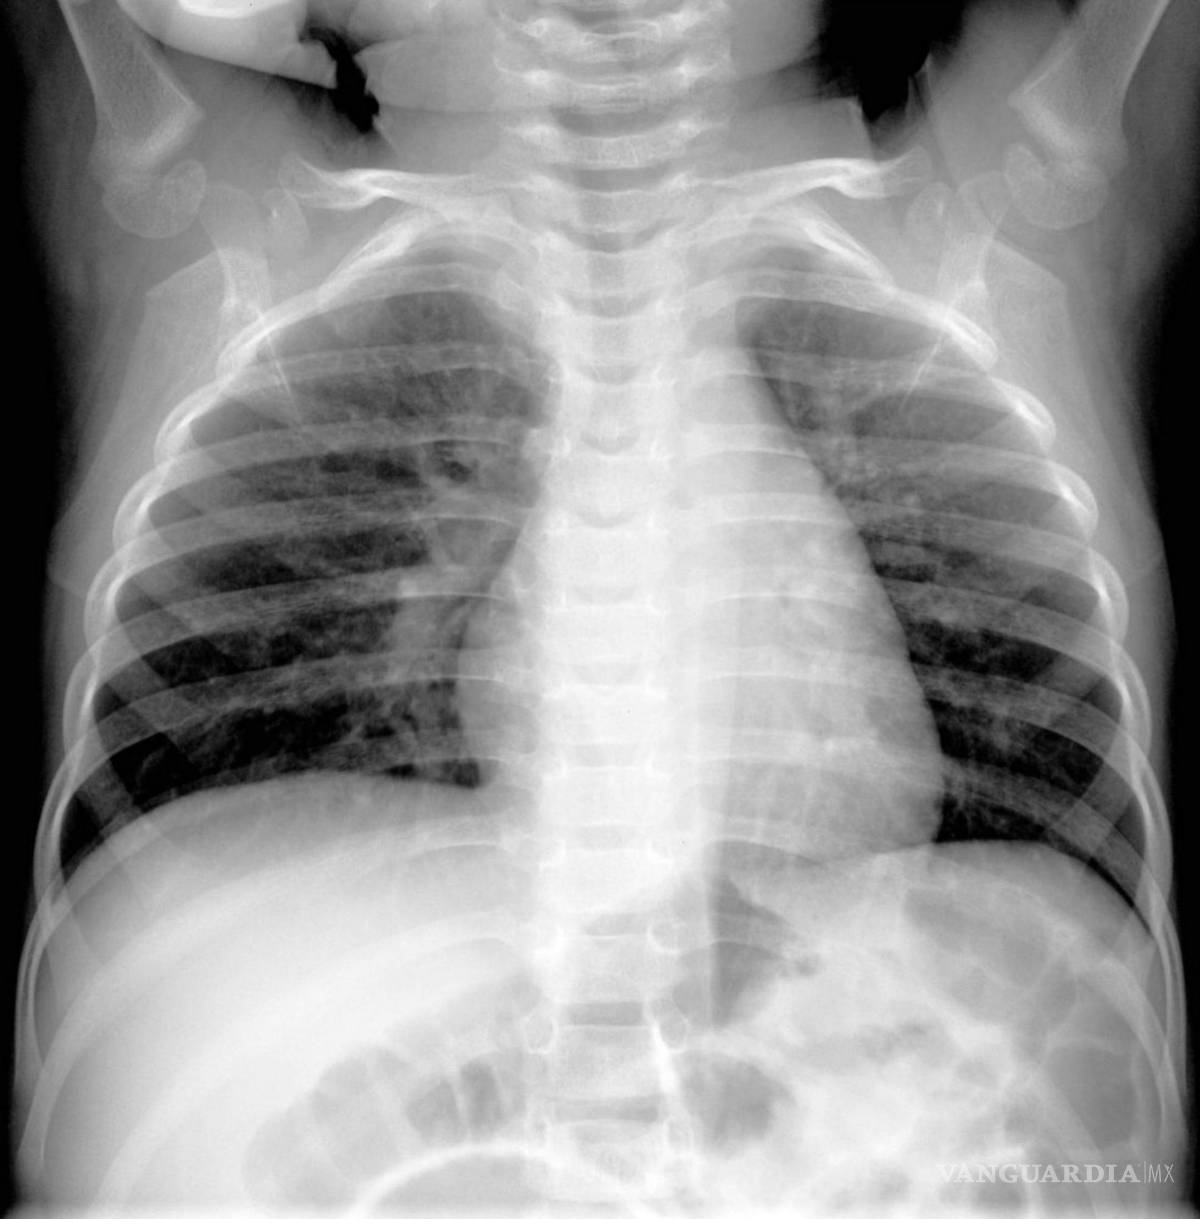

$!Una imagen de rayos X proporcionada por Hilmes et al., Pediatric Radiology, 2017 muestra a un niño de cuatro meses infectado por metapneumovirus humano.